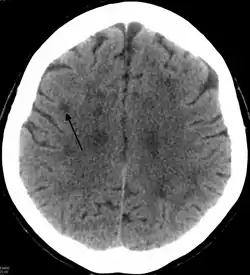

Leucoencefalopatía

El término leucoencefalopatía es usado para las enfermedades similares a las leucodistrofias.[1] Se aplica a cualquier enfermedad de la sustancia blanca del cerebro, independientemente de que su causa sea conocida o no. Puede referirse específicamente a estas enfermedades: